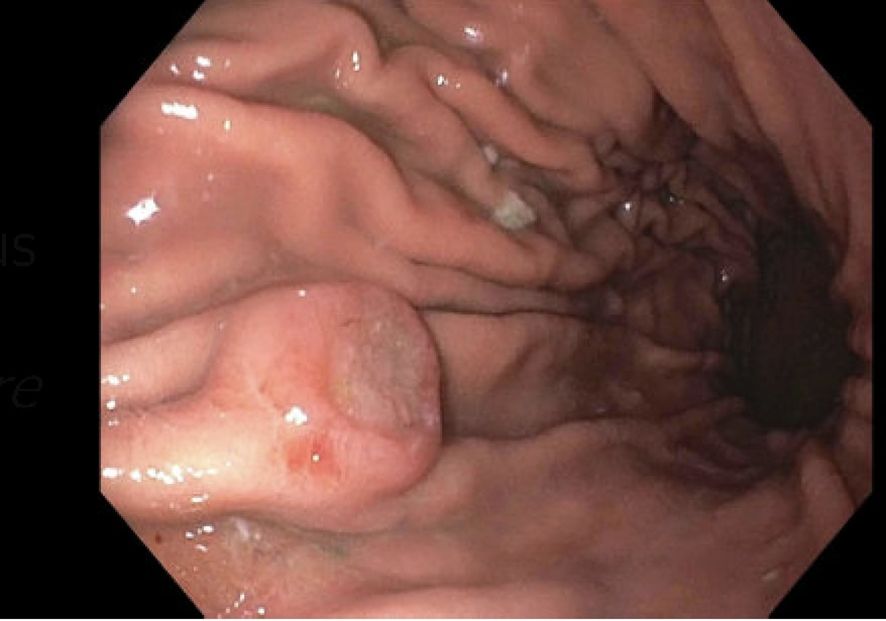

Four months after the bone marrow transplant, the patient presented with black stools, which she had been experiencing for a week. A fecal occult blood test (FOBT) was positive, prompting an EGD to rule out GI bleeding. The EGD revealed a 10-mm submucosal nodule (Figure 1). Biopsies taken from the nodule demonstrated gastric oxyntic mucosa with significant infiltration of lymphoplasmacytic cells, consistent with a plasma cell neoplasm (Figure 2). Flow cytometry analysis showed monoclonal IgG kappa plasma cells, representing 0.7% of the total cell population. Immunohistochemistry confirmed plasma cell lineage, with atypical cells positive for CD138, MUM1, CD56, CD117, and kappa light chain, and negative for CD20, cyclin D1, lambda, and immunoglobulin heavy chains (IgG, IgA, IgM, and IgD). CD3 highlighted scattered background T cells. No significant lymphoid component was present, supporting a monoclonal plasma cell neoplasm.

Figure 1. A medium-sized, ulcerated, non-circumferential mass was found in gastric body. Biopsies were taken and the mass was identified as plasmacytoma.